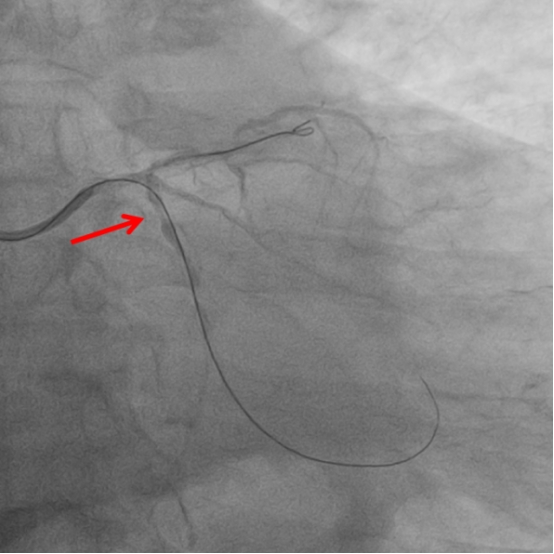

图3:右冠开通后

与死神的第一次交锋在介入室打响,胸痛中心介入团队在患者入院不到1小时便开通了右冠闭塞血管,患者胸痛症状明显缓解,术后送患者回CCU监护治疗,拟病情稳定后再处理左冠病变。